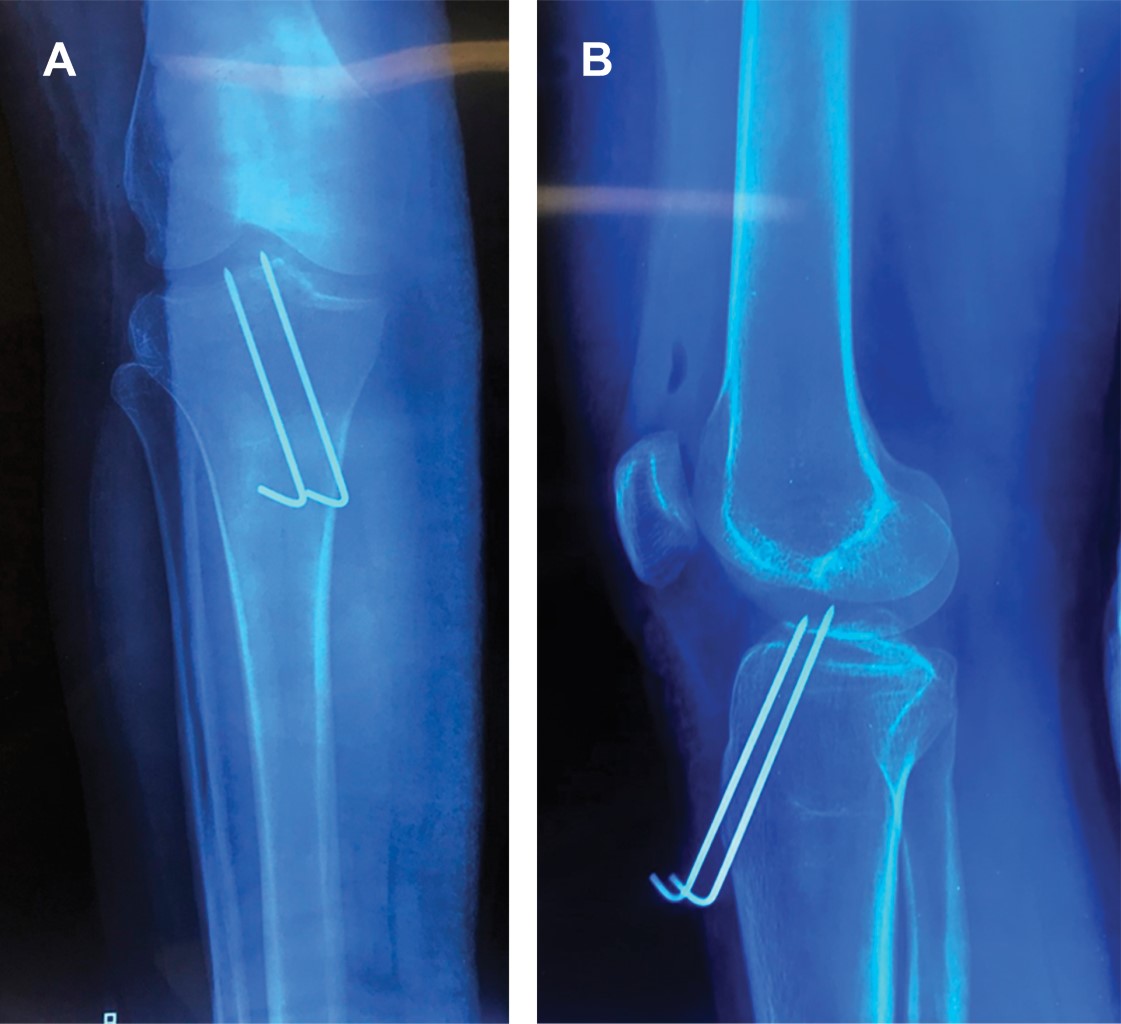

Mujer de 30 años, profesionista, sin antecedentes de importancia, que acude tras caída de 1.5 metros de altura, colisionando ambos talones contra el piso, lo que originó carga axial, hiperextensión y valgo forzado de ambas rodillas, presentando dolor inmediato e imposibilidad para la ambulación. A la exploración gran edema de ambas rodillas por hemartrosis, imposibilidad por dolor para efectuar movimientos de flexoextensión. Resto de exploración normal. Se efectúan radiografías simples de ambas rodillas, encontrando fractura de la espina tibial bilateral (Figura 1A y B), con discreto desplazamiento. Se efectúa tomografía computarizada observando al menos cuatro fragmentos y trazos de fractura (Figura 1C), correspondiendo fractura de espina tibial anterior izquierda Meyers y McKeever tipo IIIB y fractura de espina tibial anterior derecha, Meyers y McKeever tipo II. Se realiza tratamiento quirúrgico mediante artroscopia con guía para ligamento cruzado anterior, reducción y fijación con sutura de alta resistencia tipo FiberWire 2.0 y alambres de Kirschner No. 2.0 (Figura 2) en rodilla izquierda y derecha respectivamente, derivándose a rehabilitación a las tres semanas, se retiraron los alambres de Kirschner a las seis semanas en consultorio; la evolución fue satisfactoria logrando a cuatro meses de rehabilitación: marcha independiente, arcos de movimiento de 130o en ambas rodillas, con fuerza muscular 5/5 en escala de Daniels y pruebas de cajón anterior y Lachman negativas.

Figura 1